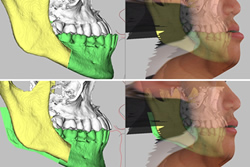

| スキャンした顎の骨を可視化して歯を移動するシミュレーションができます。 | 歯の移動をシミュレーションしたところ、歯根がぶつかってしまうことがわかりました。 | 歯根がぶつからないよう歯を動かすために、治療計画とシミュレーションを再設計します。 |